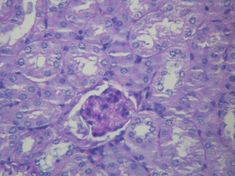

| Histopathological image of diabetic glomerulosclerosis the main cause of nephrotic syndrome in adults. H&E stain. | |